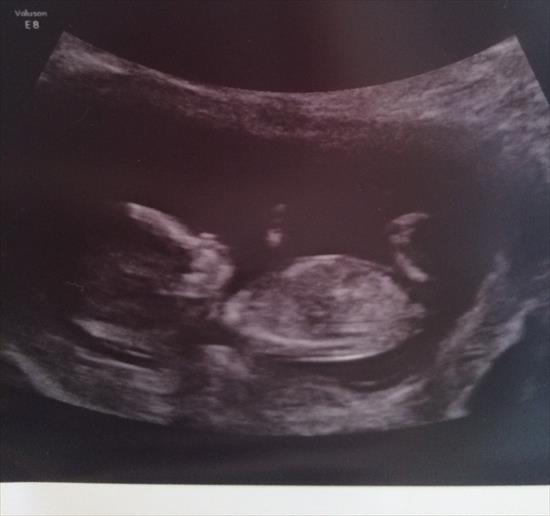

This is my second baby at 12+6. Have a beautiful son already so would love a little girl this time!!

im not seeing enough do you have any other pics?

Maybe girl